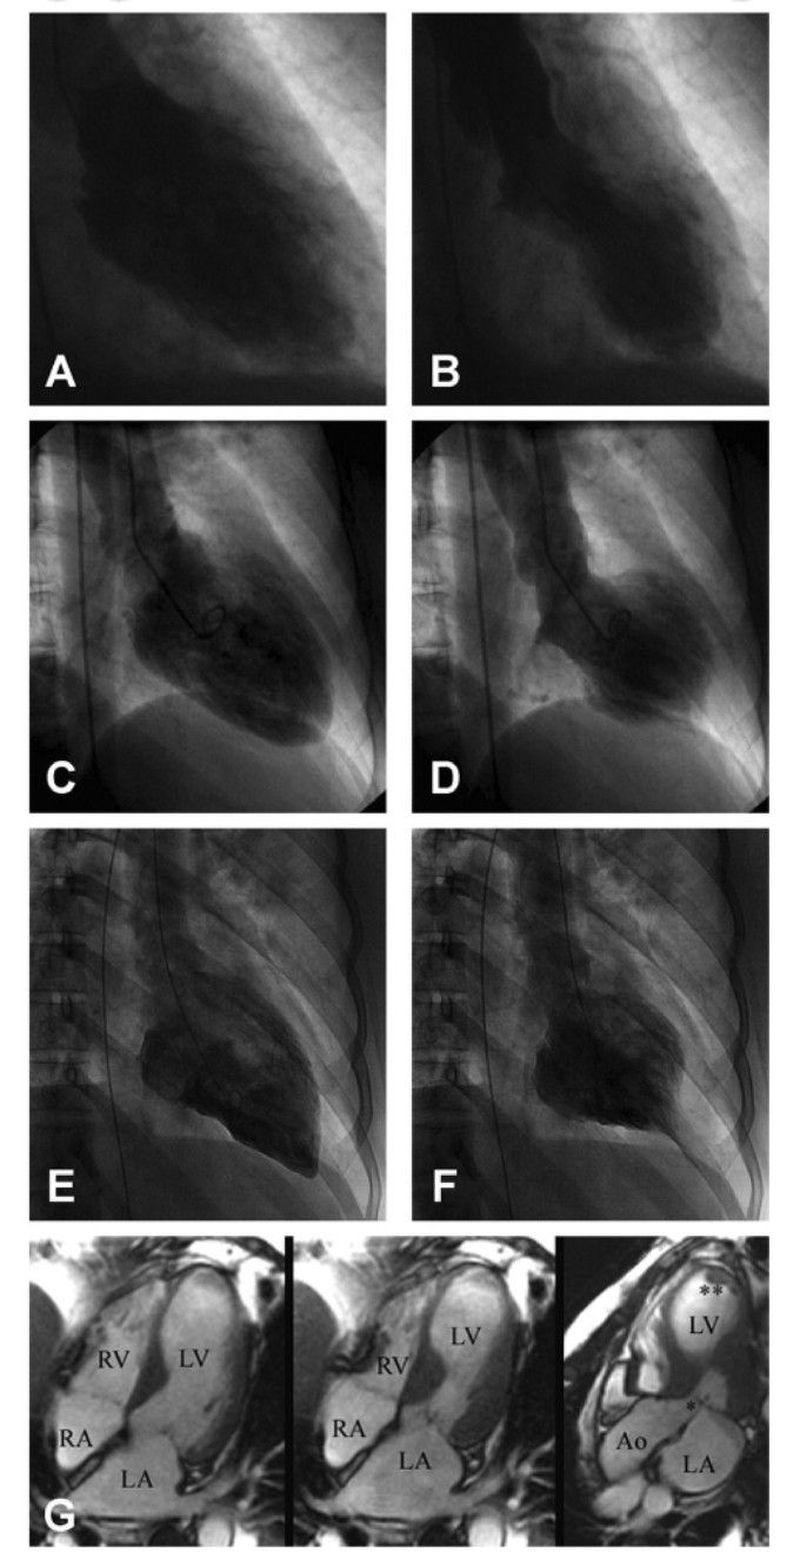

A 38-year-old healthy American woman with negative past medical history presented to our Emergency Department with chest pain developing while participating in intense outdoor physical activities (Zumba) at a fundraising event. Our patient had typical substernal chest pain induced with exercise and was relieved by sublingual nitroglycerin in the Emergency Department. The pain started after 2Β h of intensive Zumba workout. On review of her history, our patient was noted to be taking spironolactone 125Β mg once daily for hirsutism for the past year. Our patient denied any family history of cardiac disease or heart failure. She admitted to being a former occasional smoker and to drinking alcohol socially. She denied any illicit drug use. She works as a social worker, and reported that she does not experience much stress in her life and denied any "one big life-changing event" or any major stressful news. While in the Emergency Department, our patient was hemodynamically stable and an electrocardiography was performed and showed sinus rhythm with no ST elevation/depression but noted T-wave inversion in leads I and aVL, and T wave flattening in leads V1 and V2. Her troponin levels were 0.294 and 0.231 consecutively. An echocardiogram was done and showed hypokinetic apical and mid-distal walls and hyperdynamic basal walls of the left ventricle with an ejection fraction of 35-40%, consistent with apical ballooning syndrome. Cardiac catheterization was subsequently done and showed depressed left ventricle systolic function, ejection fraction of 30-35% with anteroapical dyskinesia and no evidence of coronary artery disease. Our patient was diagnosed with Takotsubo cardiomyopathy after fulfilling all four of the Mayo Clinic's diagnostic criteria and was subsequently treated with a beta blocker, and angiotensin-converting enzyme inhibitor. Our patient did not have one clear trigger for her overt Takotsubo cardiomyopathy other than the Zumba activity. Zumba is considered an activity with excessive sympathetic stimulation leading to catecholamine-induced microvascular spasm or through to direct myocardial toxicity, which is postulated to be behind the pathophysiology of Takotsubo cardiomyopathy. Another interesting finding in our patient was her use of spironolactone, as treatment for hirsutism, which is an aldosterone antagonist. Aldosterone actually potentiates the effects of catecholamine and thus activates the sympathetic system. Spironolactone can thus be considered as cardioprotective against the effects of catecholamine on the heart and that is why it is considered to be beneficial and subsequently improves mortality in chronic heart failure as described in several studies, Takotsubo cardiomyopathy or stress cardiomyopathy is characterized by transient left ventricular apical ballooning in the absence of coronary occlusion. The underlying pathophysiological mechanism is still unclear but possible causes have been proposed mainly catecholamine cardiotoxicity, followed by metabolic disturbance, coronary microvascular impairment, and multivessel epicardial coronary artery vasospasm. Takotsubo cardiomyopathy accounts for 1-2% of patients presenting with acute coronary syndrome with the majority of patients diagnosed with Takotsubo cardiomyopathy being women >β55Β years of age. Here, we discuss the case of a 38-year-old woman presenting with typical chest pain, electrocardiography changes and cardiac markers consistent with acute coronary syndrome, who was subsequently diagnosed with Takotsubo cardiomyopathy.